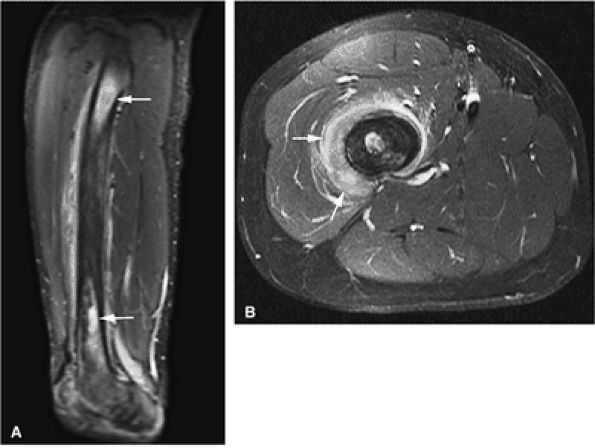

FIGURE 13.15 ● In a patient with acute lymphocytic leukemia, marrow infiltration demonstrates low signal intensity on a coronal T1-weighted image of the upper arm (A). The marrow infiltration is of high signal intensity on the corresponding coronal STIR image (B) (arrows).

|